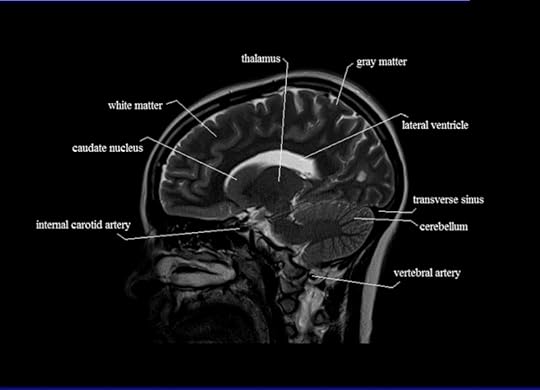

“[A] team of researchers from several institutions including Carnegie Mellon University and Harvard University developed a machine learning algorithm trained to understand neural representations of suicidal behavior, and it works with a regular functional magnetic resonance imaging (fMRI).”

The evidence can be seen in these images: